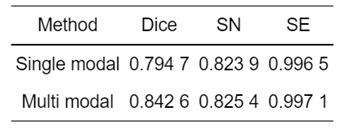

表 1为不同模态脑肿瘤检测网络训练集57例样本的三种评价指标量化分析对比.可知,多模态脑肿瘤检测网络的三种评价指标Dice、SN和SE分别提升了4.79%、0.15%和0.06%,从测试集的量化结果表明多模态的脑肿瘤检测方法更佳.

表 1 不同模态脑肿瘤检测三种评价指标对比